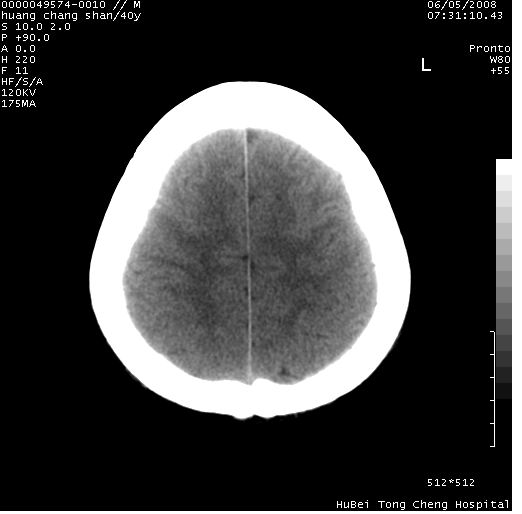

患者 m,40y。头痛,视力模糊,多饮多尿,性欲减退半年余。

行ct平扫+增强,图象如下:

2、ct表现:肿瘤呈类圆形,均匀略高密度,无囊变,无钙化。侧脑室有扩大。